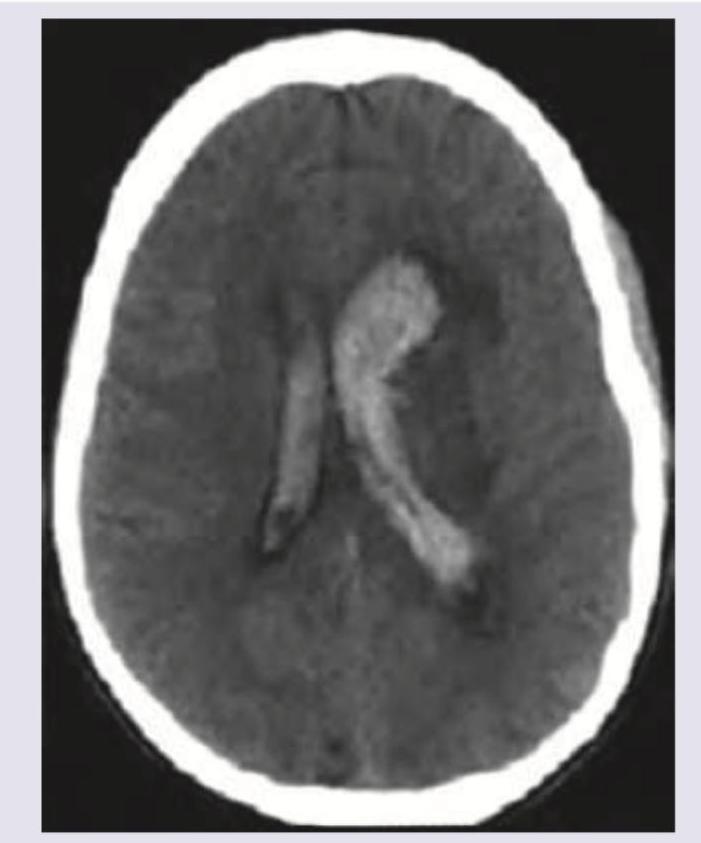

The given NCCT shows the presence of:

Explanation: ***All of the above*** - The NCCT image clearly demonstrates hyperdense (bright) blood within the brain parenchyma, distending the ventricles, and filling the sulci, indicating **intraparenchymal, intraventricular, and subarachnoid hemorrhages** simultaneously. - Head trauma can cause a combination of these bleeding patterns due to the significant forces involved, leading to diffuse axonal injury, contusions, and vessel rupture in multiple compartments. *Intraparenchymal bleed* - While there is clear evidence of hyperdense blood within the **brain parenchyma**, this option alone does not encompass all the bleeding observed. - The image shows more widespread involvement than just an isolated intraparenchymal hemorrhage. *Intraventricular bleed* - There is readily apparent hyperdensity within the **ventricles**, confirming an intraventricular hemorrhage. - However, this is not the only location of bleeding on the scan. *Subarachnoid bleed* - The image shows hyperdensity within the **sulci**, consistent with blood in the subarachnoid space. - Like the other options, this is only a partial description of the overall bleeding pattern seen.